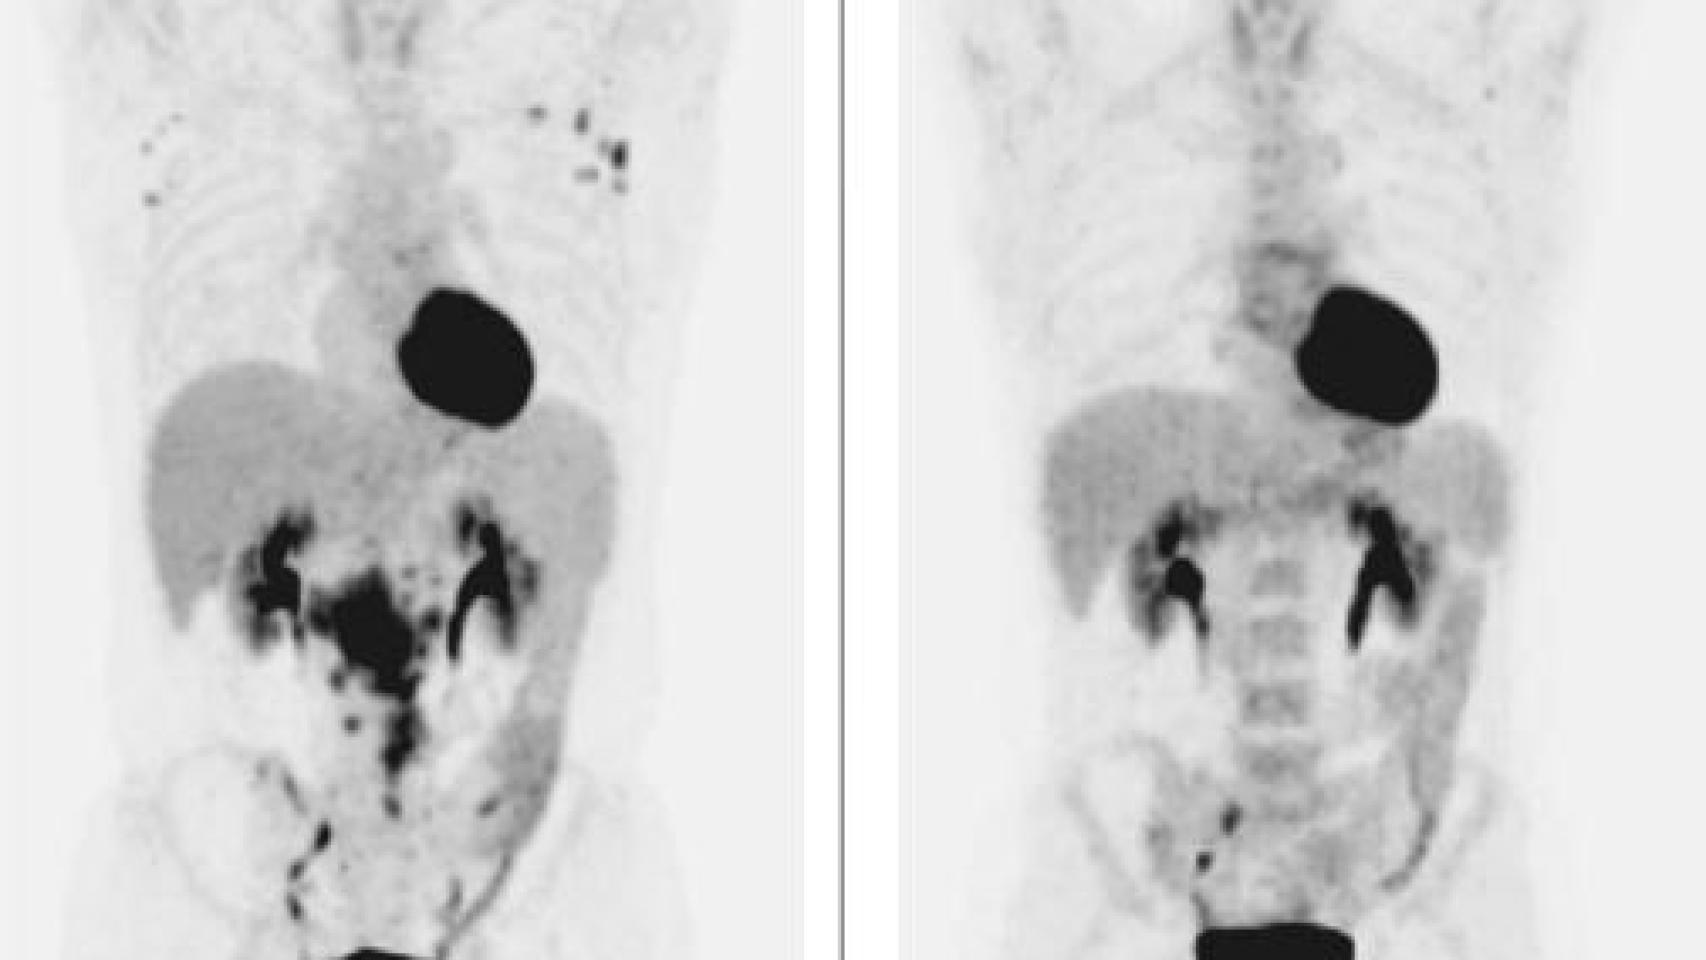

El tumor, antes y después del tratamiento para la hepatitis C.

El tumor, antes y después del tratamiento para la hepatitis C. The New England Journal of Medicine

"El escaner nos pilló totalmente por sorpresa y mostraba claramente que ya no había enfermedad", comenta O'Brien, que recuerda muy bien cuando se lo comunicó al paciente. "Estaba encantado. Cuando le vi después de acabar su tratamiento para la hepatitis C y decirle que éste había tenido éxito, me comentó que ya no sentía el bulto en su cuello ni en su abdomen, pero que seguramente serían imaginaciones suyas", subraya.

Nada más lejos de la realidad. La prueba de diagnóstico por imagen demostró que esa percepción del enfermo -ya sano- era real. Y así siguió siéndolo en la siguiente revisión, a los seis meses. En septiembre de 2016, el protagonista de esta historia seguía sano y sin evidencia de recurrencia de la enfermedad. Se trataba del primer caso de curación de un tumor maligno de este tipo tras aplicar las nuevas terapias contra la hepatitis C.